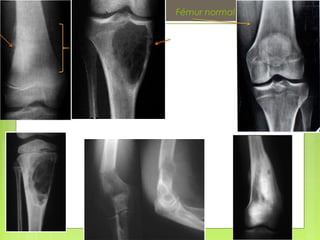

ESTUDIO DE UNA RX.

 Partes blandas, periostio, cortical,

medular ósea,

 Áreas comprometidas (diáfisis, metáfisis o

epífisis),

 Estado del cartílago de crecimiento y,

finalmente, afectación articular.

 2

 1

 3

 4

 6

 5

 7

 8

 9

Fémur normal